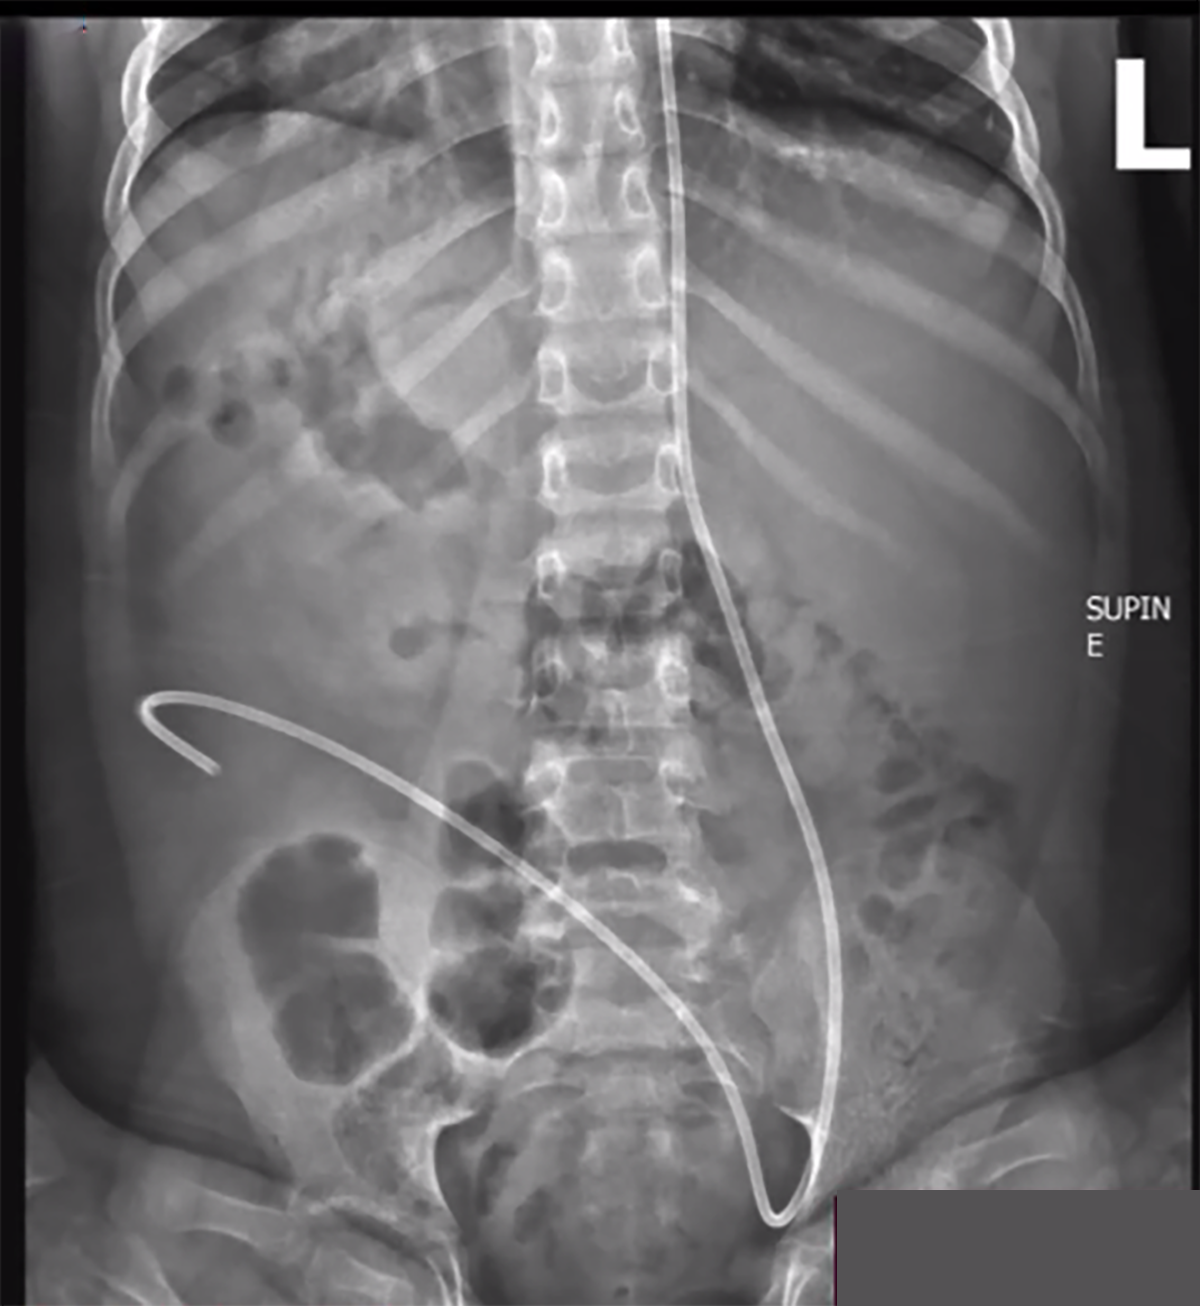

alternative diagnosis for lines and tubes